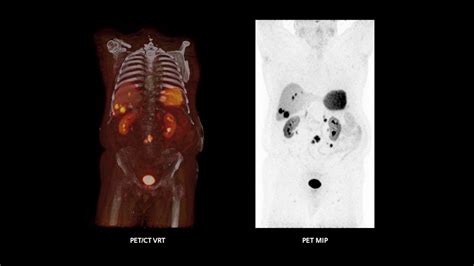

At its core, a Pet Ct scan is designed to provide both functional and structural information. While a traditional CT scan uses X-rays to create detailed pictures of organs and tissues, a PET scan uses a small amount of radioactive tracer to highlight areas of high metabolic activity. This is particularly crucial in oncology, as cancer cells often exhibit higher metabolic rates than healthy cells.

When these two technologies are combined into a single Pet Ct machine, the results are fused together. This allows doctors to pinpoint the exact location of a biological abnormality and observe its physical size and shape simultaneously. The fusion of this data is what makes it a gold standard in modern diagnostics.

• Oncology: Used to diagnose, stage, and monitor the effectiveness of cancer treatments.